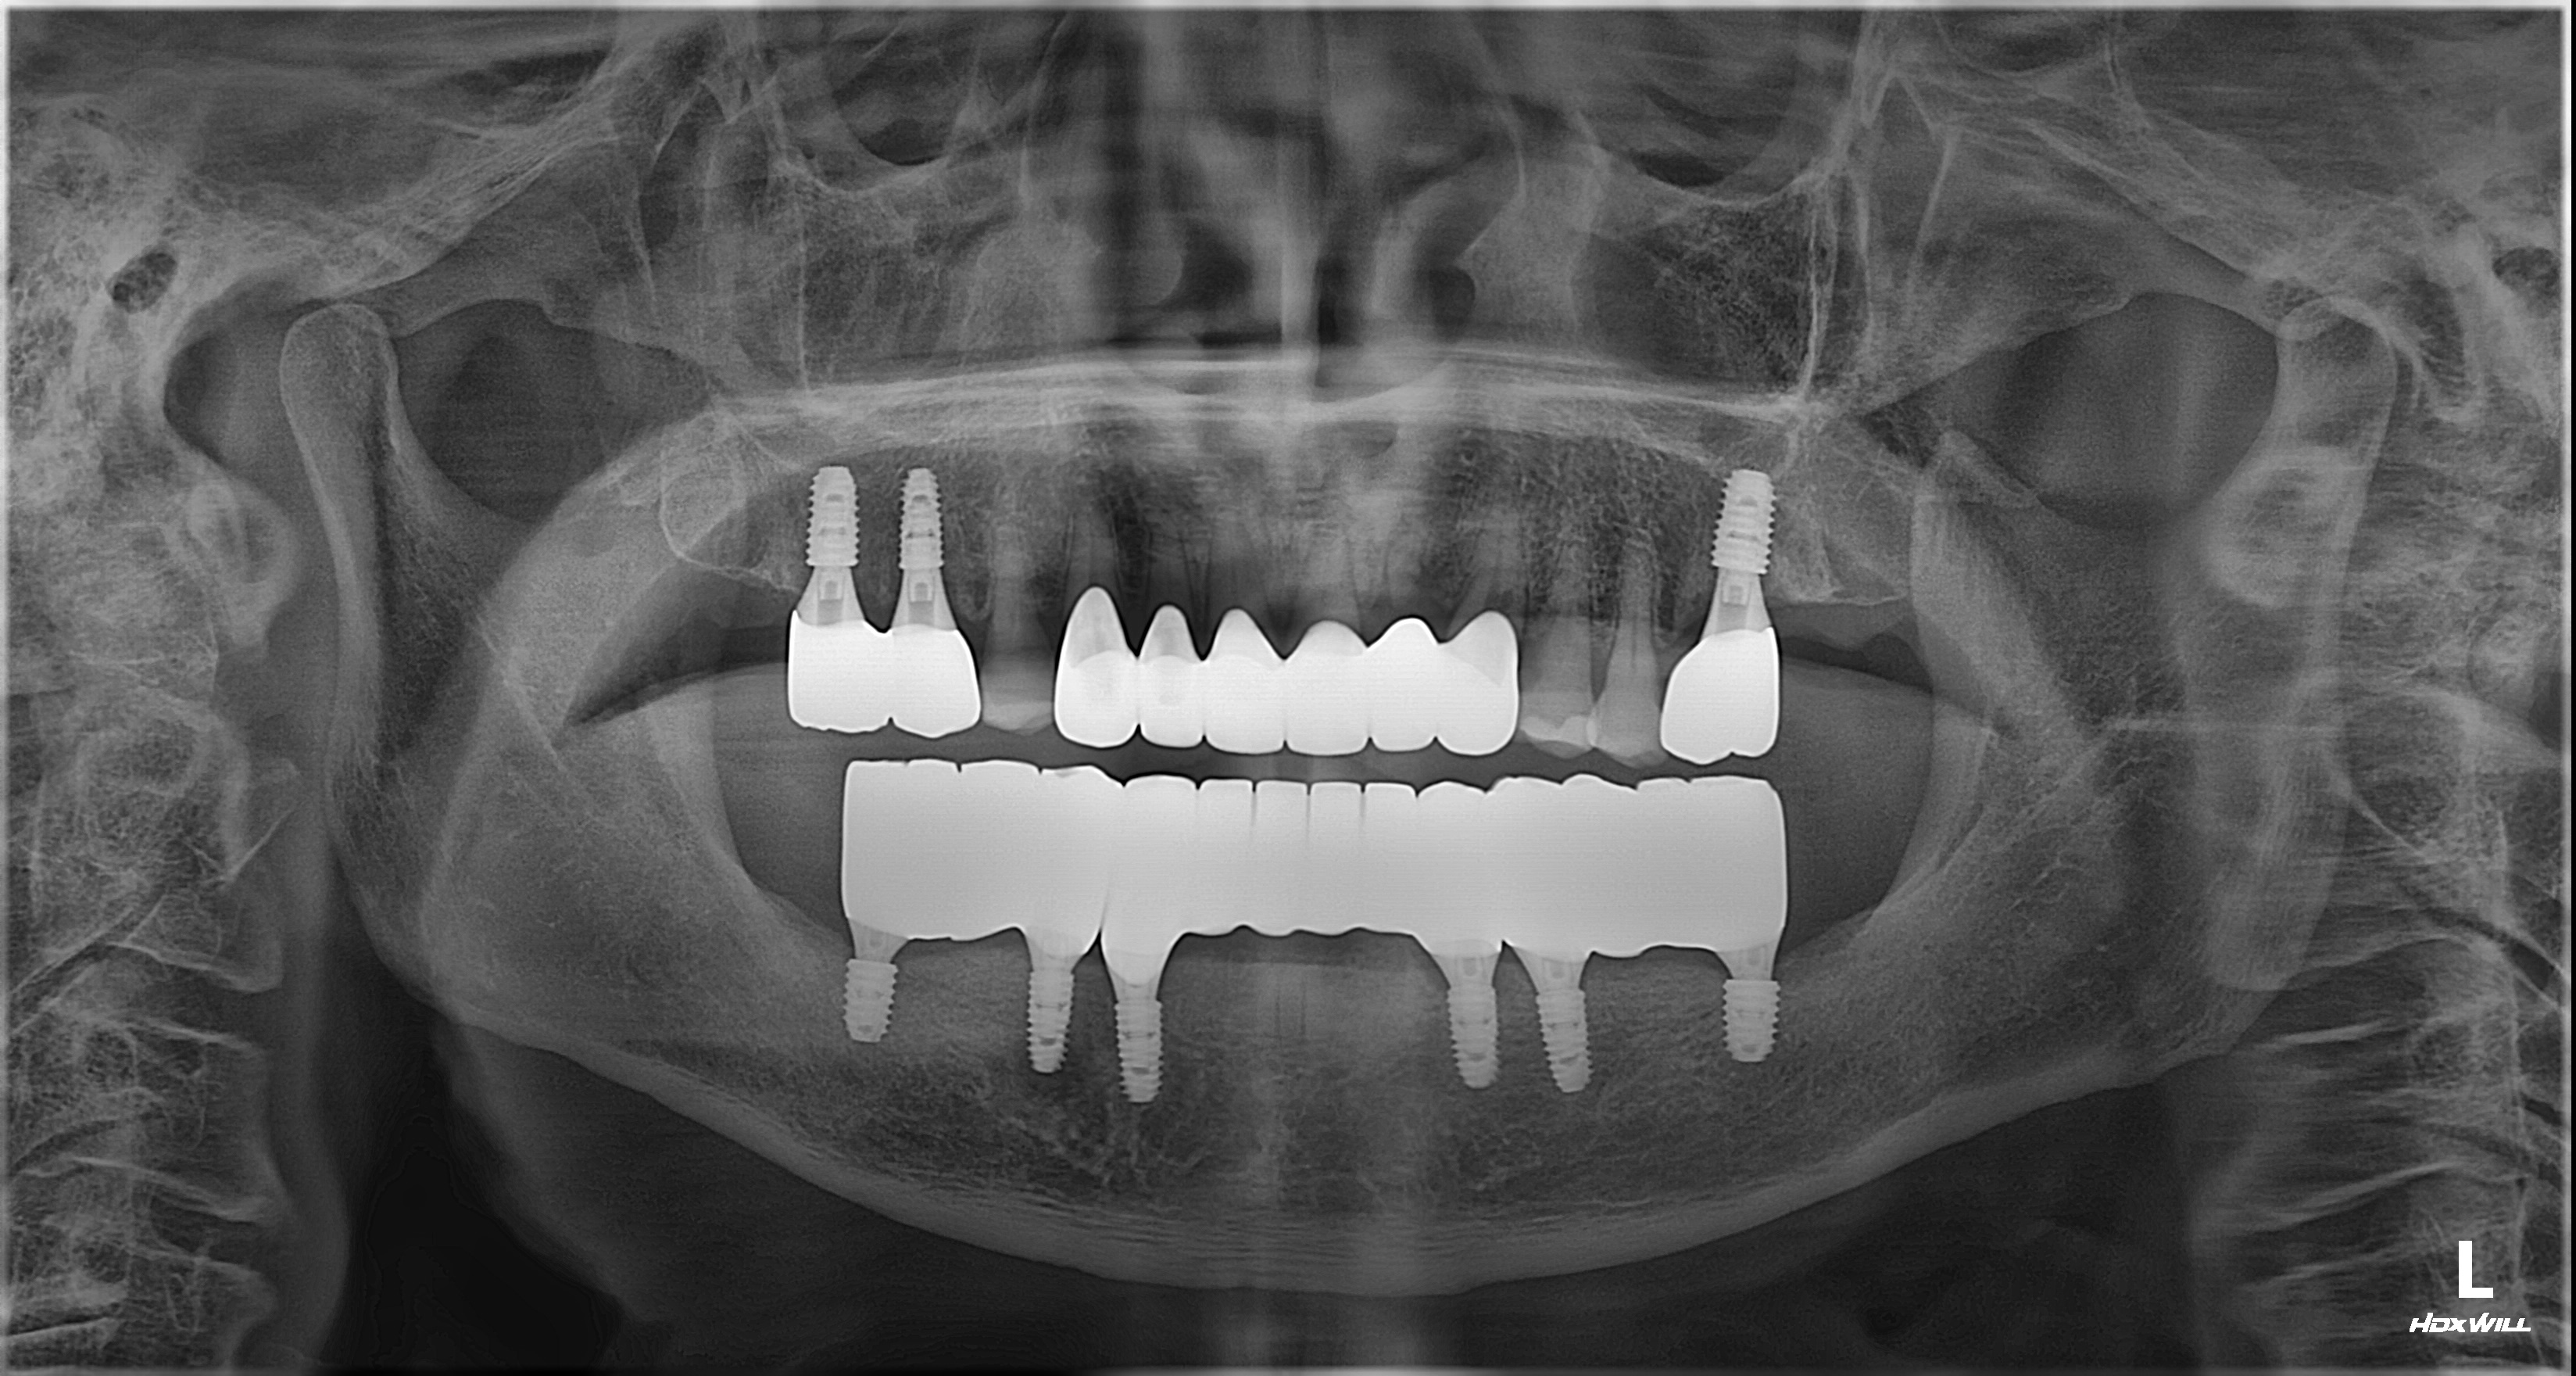

촬영일시: 2025.03.29. [ 치료기간: 2024년 10월 05일 ~2025년 03월 29일 ] ※ 365서울앞선치과의원의 모든 컬럼은 각 진료과 의료진이 직접 작성합니다. 365서울앞선치과의원 임상 케이스 게시물은 환자분께 의학적으로 정확하고 상세한 정보를 드리기 위해 각 진료과 의료진이 직접 작성하며, 모든 증례 사진은 본원 의료진이 직접 시술한 증례를 촬영한 것으로, 의료법 제23조, 제56조에 의거하며 환자분의 동의를 얻어 포스팅에 사용하였습니다. 또한 해당 케이스는 본 환자분의 치료 결과이며, 환자 상태에 따라 치료의 결과는 달라질 수 있습니다. |